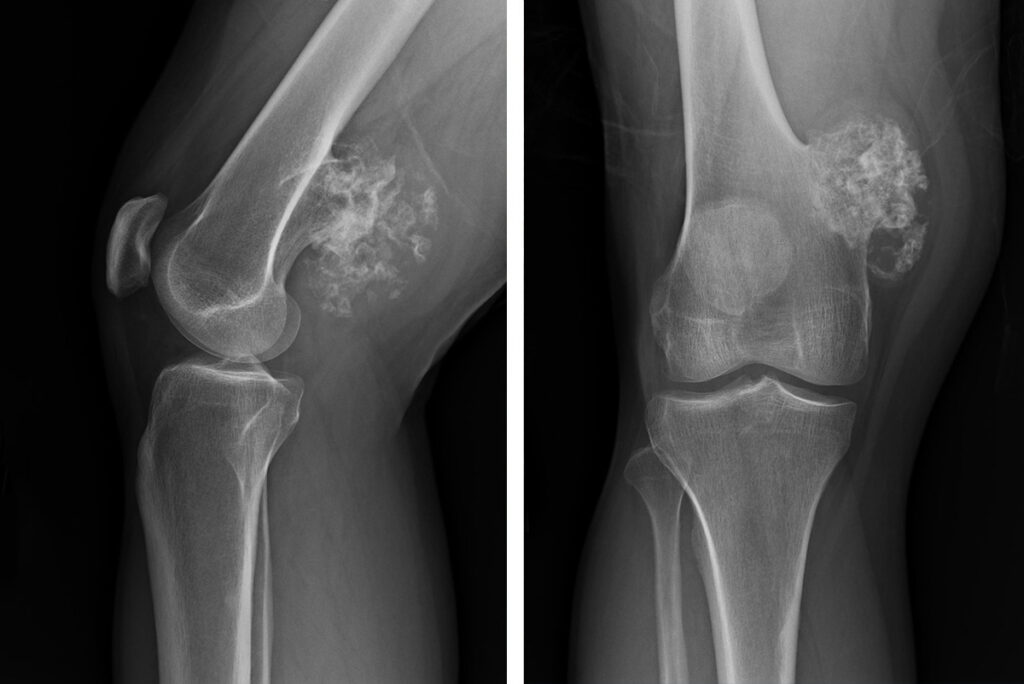

Osteosarkom, kemiklerde en sık görülen primer kanser türüdür. Genellikle çocuklar ve genç yetişkinlerde görülür. Bu tür kanser genellikle büyük kemiklerde, özellikle diz ve omuz gibi eklem bölgelerinde ortaya çıkar.

Kemik kanseri tanısı, doktorların hastanın tıbbi geçmişini ve fiziksel muayenesini değerlendirerek konur. Röntgen, ilk değerlendirme için kullanılan yaygın bir yöntemdir. Kemiklerdeki anormal değişiklikleri gösterebilir. Daha ayrıntılı görüntüler sağlamak için MR ve bilgisayarlı tomografi (BT) taramaları kullanılabilir. Kanserin türünü ve evresini belirlemek için kanserli bölgeden hücre örnekleri alınarak laboratuvar ortamında incelenir.